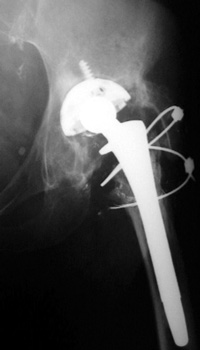

Broken, frayed, and disintegrating cerclage cables

Side plate placed for periprosthetic fracture, now broken with loss of reduction of femur fracture

6/97

11/02